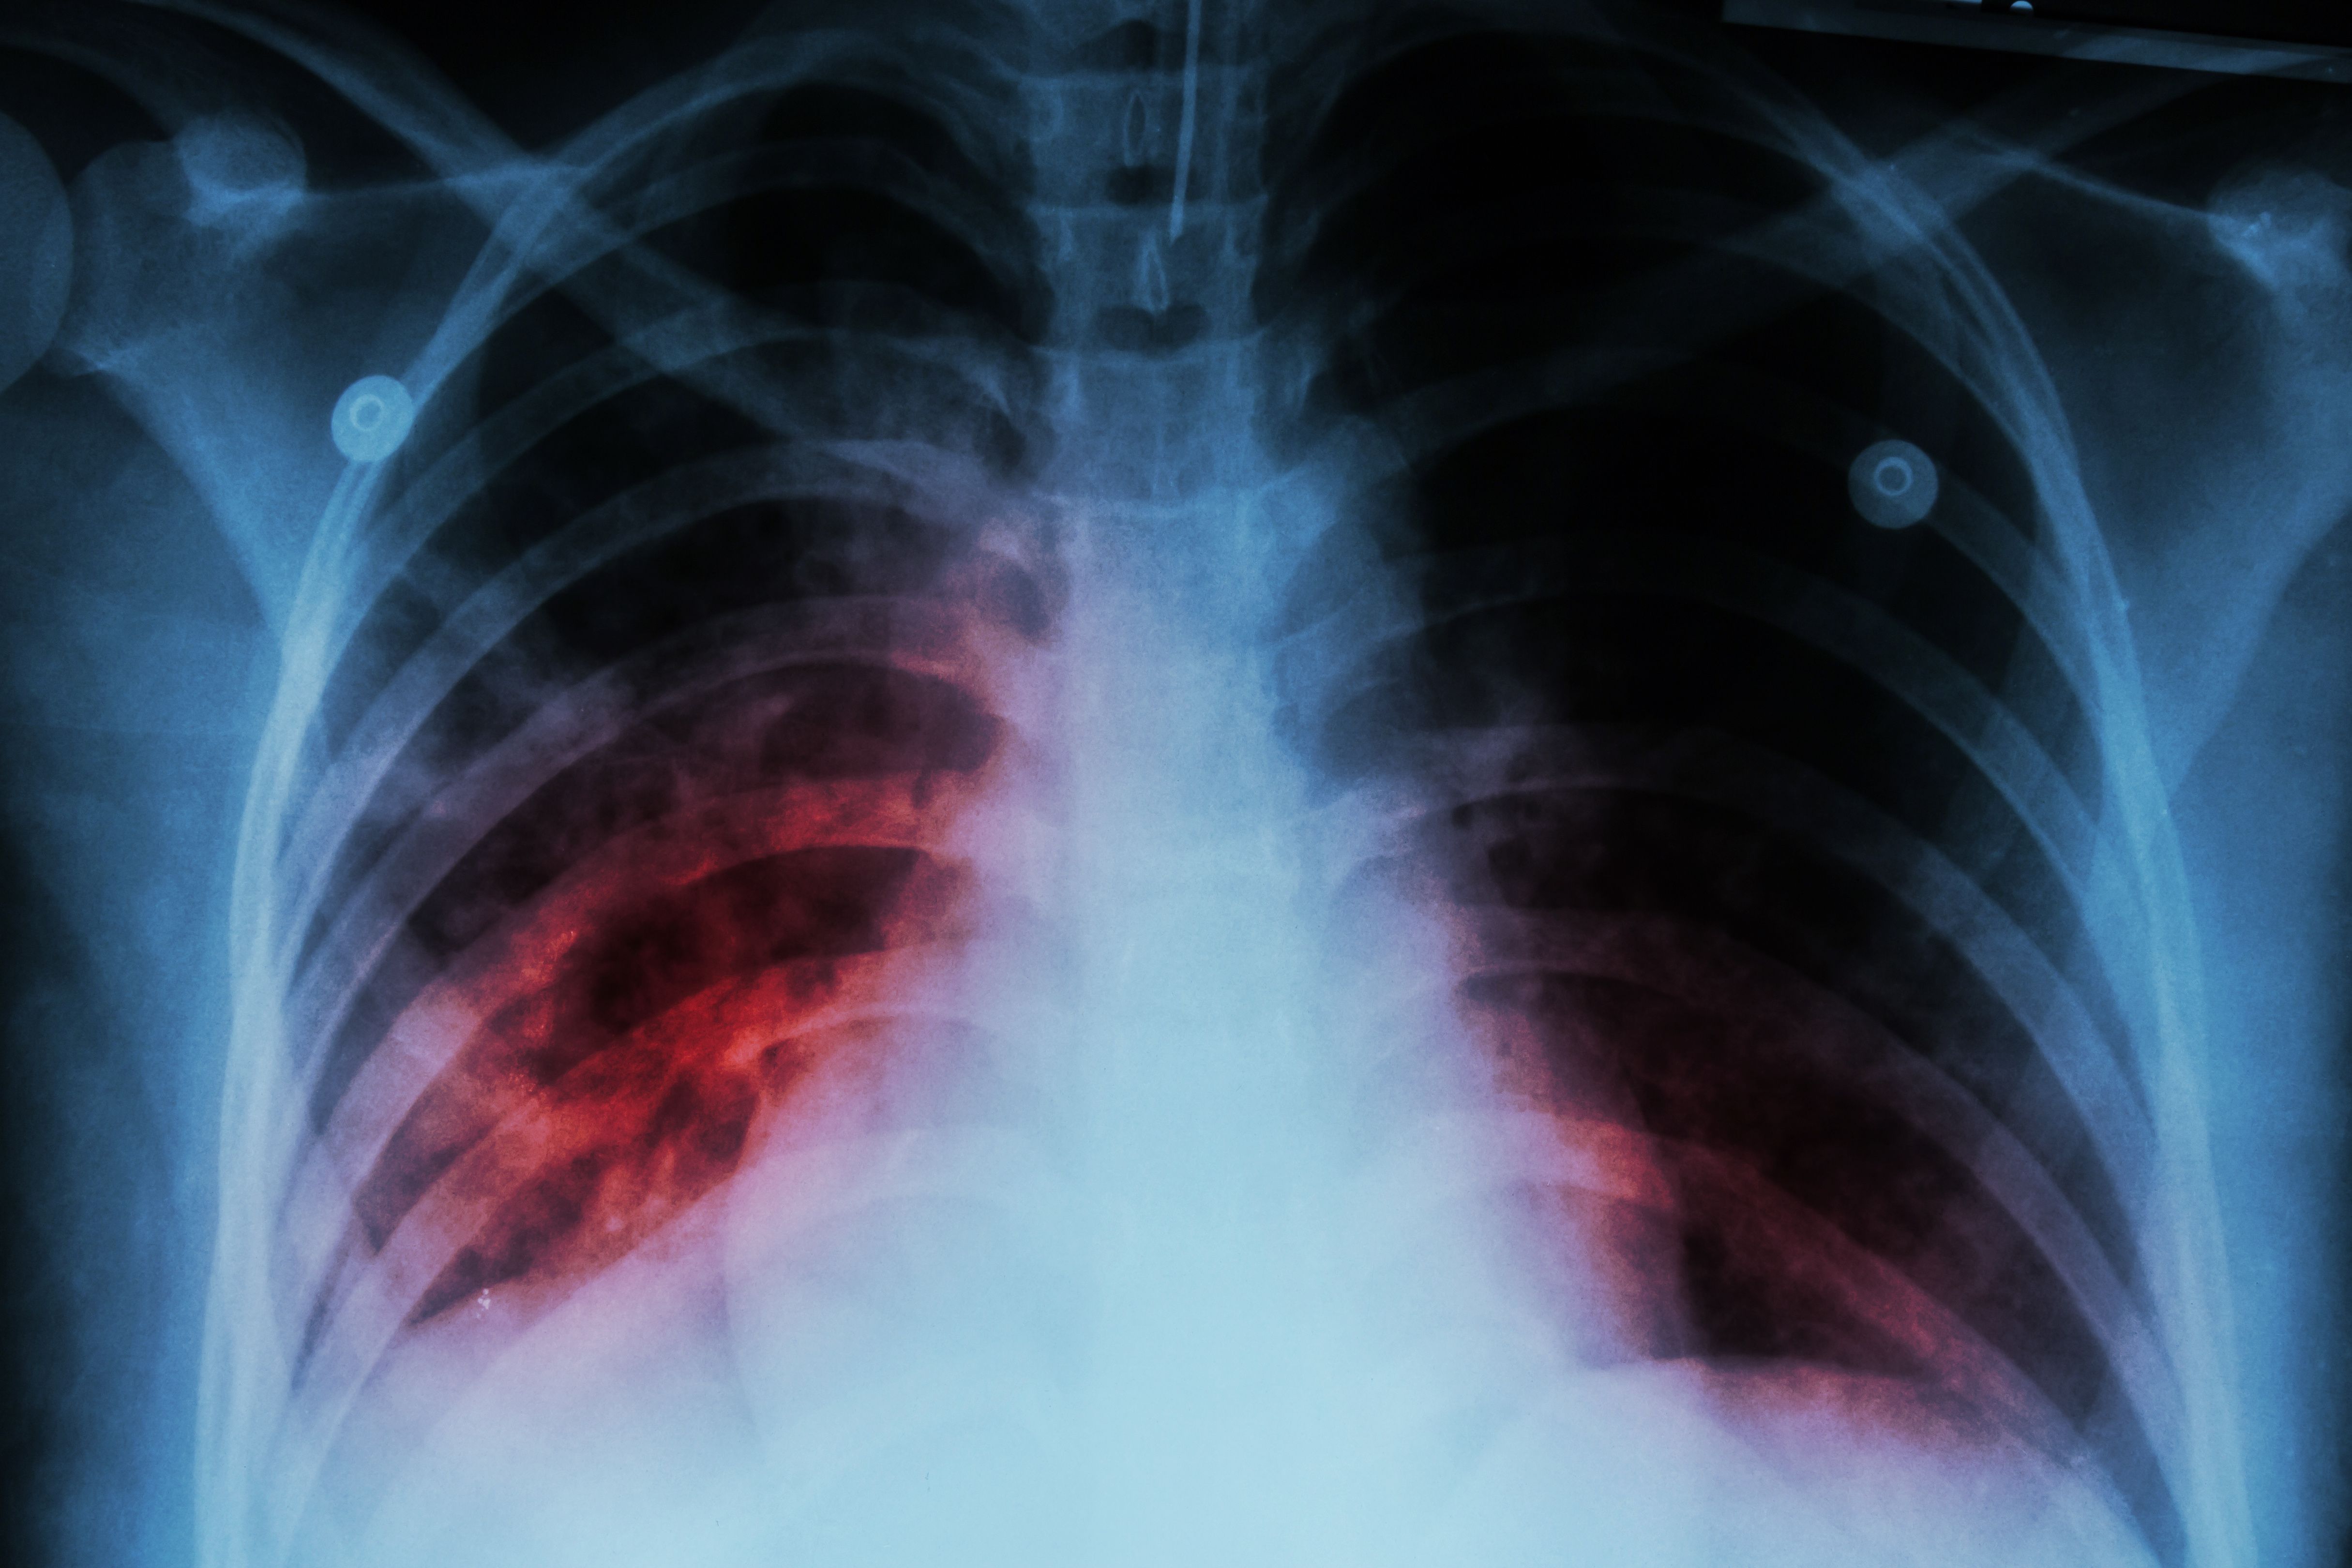

Pulmonary hypertension due to interstitial lung disease (PH-ILD) has long been connected to high rates of respiratory failure and death.

A new study conducted by researchers at the United Therapeutics Corporation in Durham, NC, looked to characterize PH-ILD disease burden by analyzing healthcare resource utilization (HCRU) and cost data.

The study, published July 11, 2024 in BMC Pulmonary Medicine, discovered the hospitalization among patients with PH-ILD more than doubled over a 2-year period; additionally, total health care costs also more than doubled after the same 2 years.